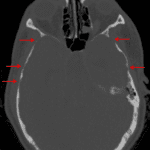

CT

- Multifocal areas of calvarial thinning, particularly involving the bilateral greater sphenoid wings and squamous temporal bones and the cribriform plate